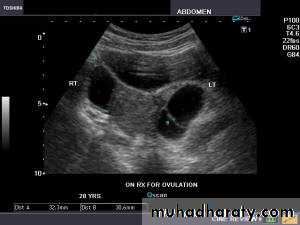

Use of infertility workupSerial measurement of ovarian follicular diameter (folliculometry) and endometrial thickness are done using TVS.

Ultrasound can provide presumptive evidence of ovulation. Following ovulation, internal echoes appear and free fluid is observed in pouch of Douglas.

To detect correcting time of ovulation by folliculometry in conjuction with plasma oestradiol.